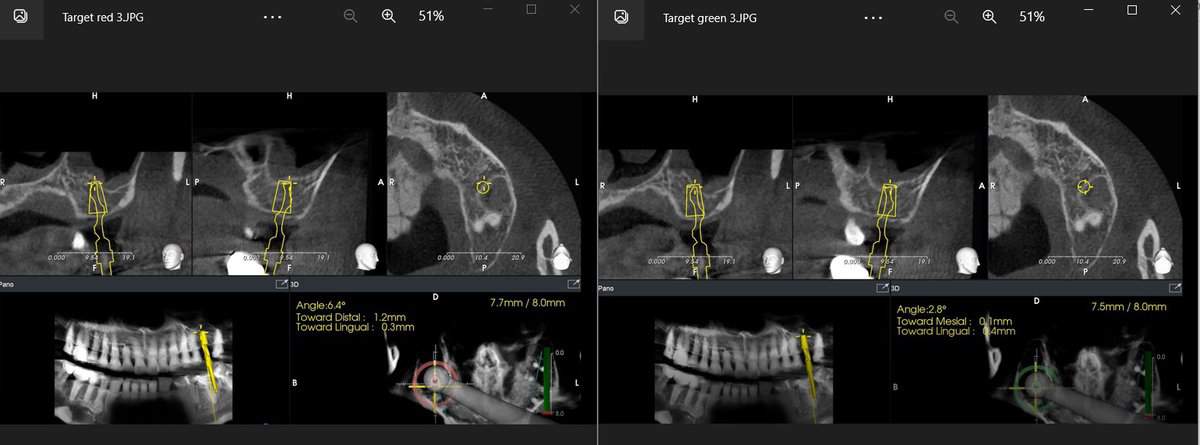

Half a dozen major dynamic navigation systems focused in implant dentistry are now in the market, two of which are backed by leading implant manufacturers Straumann and Nobel Biocare. All systems use in principle the same optical tracking technology, but they each have its own proprietary design features which can impact ergonomics, accuracy, user experience, overall efficiency and cost effectiveness. The competition is going to be fierce and whether a clear winner is going to emerge in the end is up to everyone to speculate.

In a recent randomised clinical trial static and dynamic computer assisted implant surgery were combined and used simultaneously while placing dental implants. The result was increased accuracy, even beyond the level that static or dynamic CAIS alone can offer. This can lead to even more precise surgeries, It comes however with an increased cost and time commitment.

How can you combine static and dynamic? Well that was not too difficult actually. In principle, you have to follow the workflow of the static, print the guide accordingly and then register and calibrate the guided surgery drills for the dynamic CAIS before the surgery. In the surgery the operator will place the surgical guide and continue with the drills as usual, only now with the visual aid of the correct angle and depth also displayed in real time.